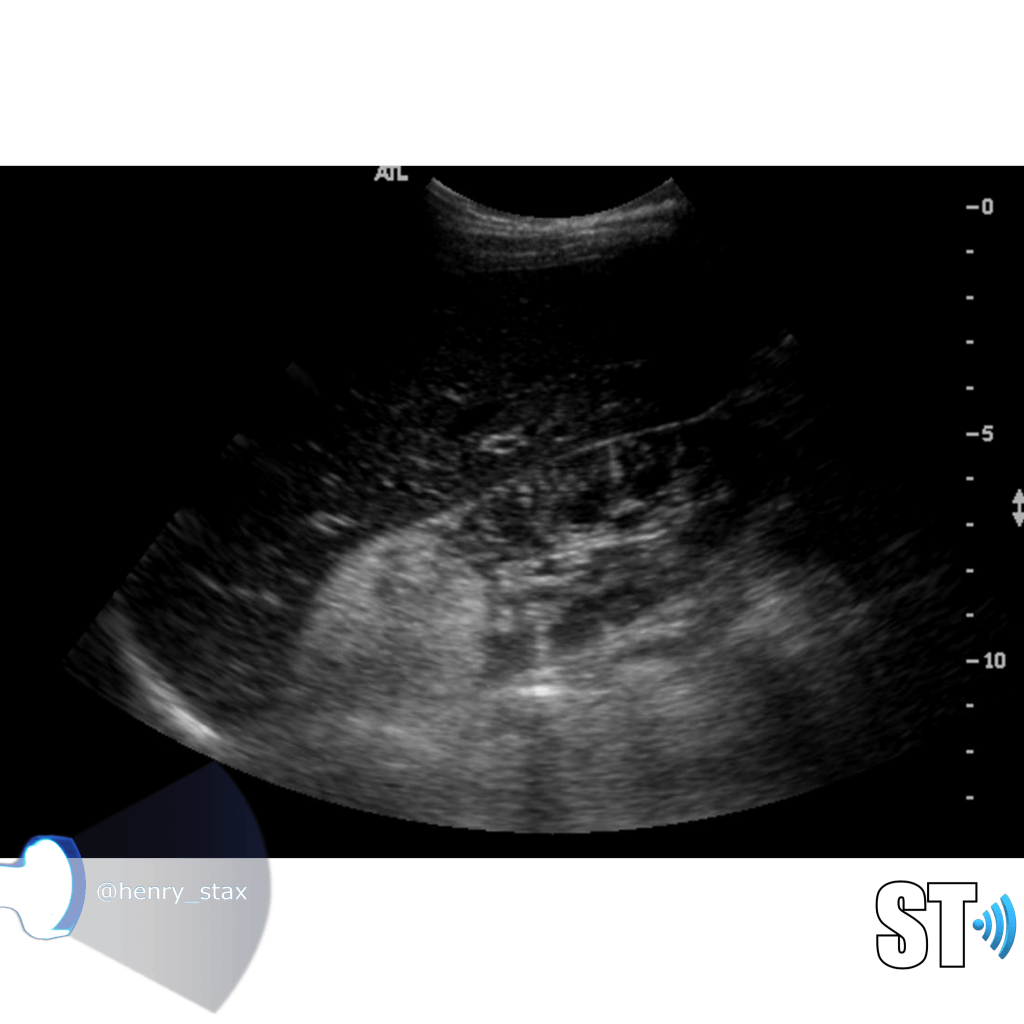

ARPKD

Autosomal Recessive Polycystic Kidney Disease (ARPKD) Typically presents around birth, though it can present later in childhood. Cases that develop later have a propensity to be associated with hepatic fibrosis. ARPKD is transmitted in an autosomal recessive pattern meaning two copies of an abnormal gene must be present in order for the disease or trait to develop.

- Infantile

- Kidney enlargement (sometimes massive)

- >80% liver cysts

- Multiple organs affected

- Hyperechoic